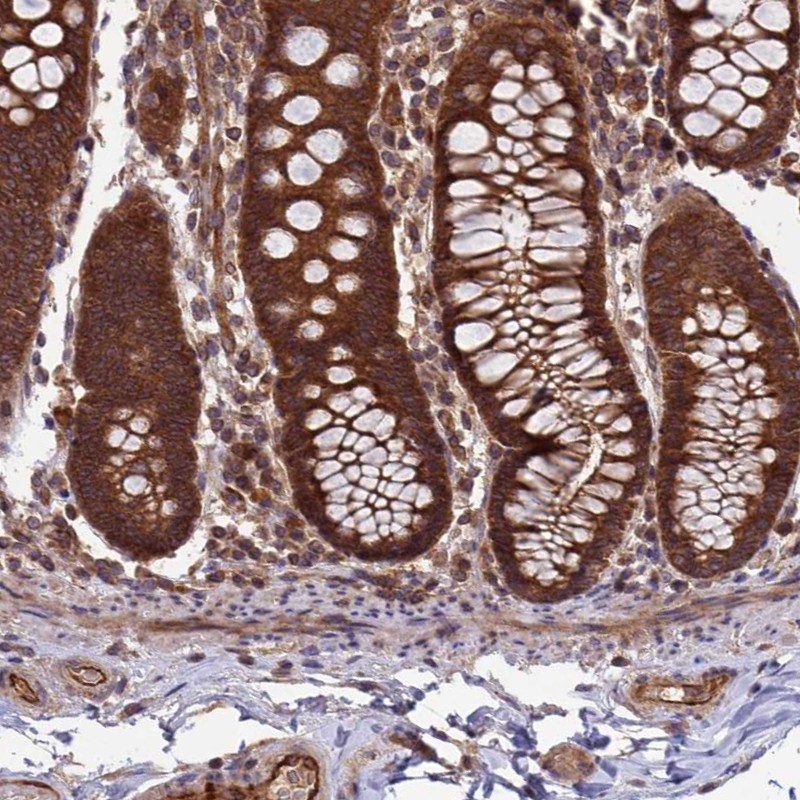

Immunohistochemical staining of human colon shows strong cytoplasmic positivity in glandular cells.